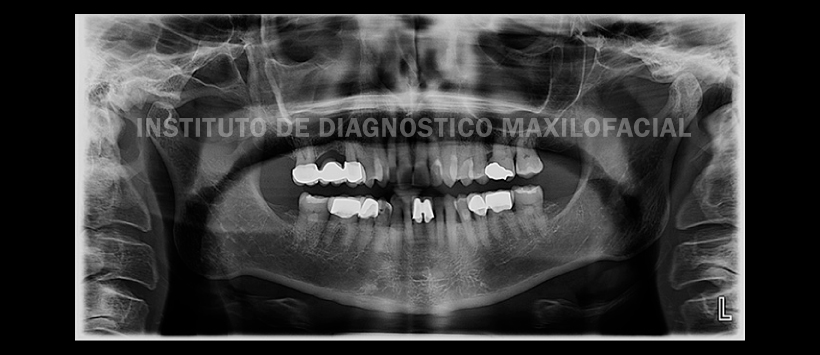

A la evaluación de la radiografía panorámica (Figura 1) se aprecia opacificación del seno maxilar derecho y engrosamiento de la línea innominada-“U del malar”- piezas 17 y 15 con coronas protésicas pilares de puente con engrosamiento periodontal y no se aprecia procesos osoteolíticos periapicales.